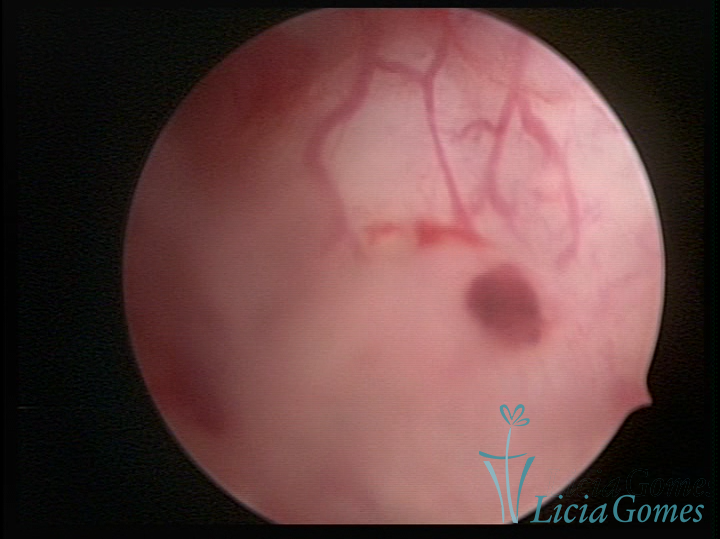

ADENOMIOSE

É a presença de tecido endometrial na camada muscular do útero

A vídeo-histeroscopia permite diagnosticar às lesões próximas às camadas miometriais superficiais, próximo ao endométrio visualizando lesões de coloração violácea, circunscritas, ou acastanhadas com conteúdo achocolatado.